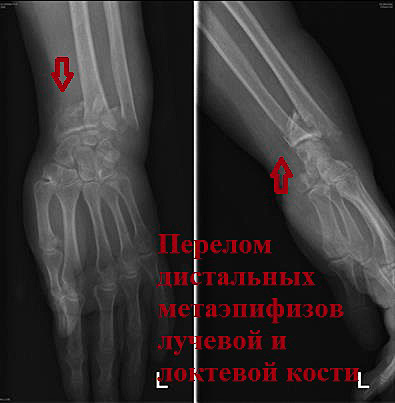

Пациентка М. 70 лет. Упала в быту на улице. При поступлении в клинику диагностированы многооскольчатые переломы дистальных метаэпифизов локтевой и лучевой кости. После закрытой репозиции сохраняется смещение отломков.